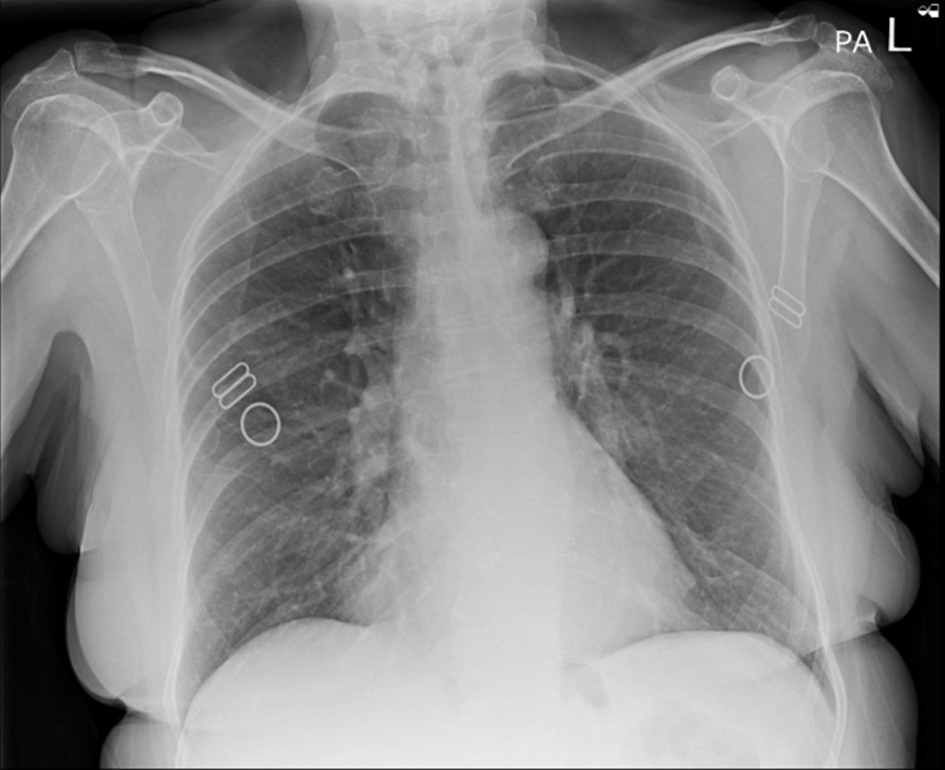

On examination, the patient was found to have externally rotated and shortened left leg and bilateral lower leg edema. Initial abdomen examination revealed soft non-tender abdomen. X-ray imaging of pelvis revealed subcapital fracture of the left neck of femur. She was afebrile (36.4 °C) with heart rate of 68 bpm, oxygen saturation of 97%, and blood pressure of 170/89 mm Hg. On auscultation, the chest was clear bilaterally with a midline trachea and no crepitus. The patient was subsequently diagnosed with non-traumatic neck of femur fracture and underwent hemiarthroplasty of the left leg under general anesthetic. Postoperative examination of the patient revealed soft non-tender but distended abdomen with absent bowel movement. The patient reported no discomfort, but it remains unclear whether this is due to postoperative analgesia or her continuing pregabalin use. Her postoperative analgesia included codeine 30 mg four times a day with breakthrough oral morphine 10 mg as required. The patient opened her bowels on postoperative day 2. Initial supine chest radiograph (CXR) revealed shallow lung expansion with elevated hemidiaphragms more in the right side (Fig. 1), compared with CXR performed 3 years ago which was normal (Fig. 2). Repeat anterior-posterior chest radiograph conducted the second day postoperatively showed gas filled loops of bowel beneath the hemidiaphragms with a distended bowel (Fig. 3). Although pneumoperitoneum was the primary concern, it was crucial to rule this out using both clinical and imaging studies. It remained unclear whether a small bowel obstruction or an abscess was present in X-ray. Computed tomography (CT) was conducted which revealed interposition of bowel between the liver and diaphragm which is consistent with Chilaiditi sign and small compressive atelectasis in the lung basis. The CT scan ruled out the presence of any abnormal bowel dilation, pneumoperitoneum, and abdominal mass (Fig. 4). The patient received medical optimization for bone protection, intensive physiotherapy, and occupational therapy input. She was discharged 13 days postoperatively with twice-daily care support. Reports in her 3-month outpatient orthopedic review remarked on her good recovery. No specific follow-up for her Chilaiditi syndrome was required and her recovery from this was uneventful.

Figure 2. Anterior-posterior chest X-ray, 3 years prior to presentation showing normal chest X-ray and no gas loops in the hemidiaphragm.